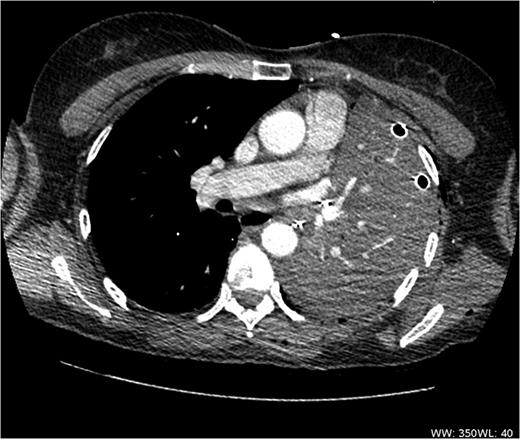

A 57-year-old woman with a left upper lobe mass was referred to our institution for lung resection. Preoperative computed tomography (CT) and positron emission tomography were consistent with lung cancer. Pulmonary function tests revealed a forced expiratory volume in 1 s of 1.64 l (64% predicted), forced vital capacity of 3.1 l (104% predicted) and TLCO of 97% predicted. The patient underwent an uncomplicated left upper lobectomy through open thoracotomy. The fissures were complete, and the inferior pulmonary ligament was mobilized in part. A systematic nodal dissection was performed. She was extubated immediately after surgery and was transferred to the ward as per routine practice. Post-operative chest radiograph revealed satisfactory expansion of the left lower lobe (Fig. 1). On the first operative day, the patient remained haemodynamically stable, without systemic upset, but developed atrial fibrillation with tachycardia. Chest X-ray demonstrated complete opacification of the left hemithorax with normal position of the left hemidiaphragm (Fig. 2). Urgent rigid bronchoscopy revealed narrowed left lower lobe bronchial orifice and the bronchoscope could not pass through. The left upper lobe bronchial stump was intact. Immediate exploratory thoracotomy was performed. At surgery, the left lower lobe had undergone a 180° anti-clockwise torsion at its brochovascular pedicle. The lung parenchyma was very fragile and haemorrhagic, compatible with early venous infarction, hard with a dark reddish surface. Torsion of the lower lobe was corrected and lower lobe was sutured to pericardium, in order to further investigate the anatomy, and determine whether completion pneumonectomy could be avoided. Her AF resolved with restitution of the lobe. A minitracheostomy was inserted prophylactically. However, over the course of the first few post-operative hours, the patient became progressively more hypoxic and tachypnoeic. CT was performed, demonstrating acute obstruction with possible angulation of main pulmonary artery and complete obstruction of left main bronchus (Fig. 3), reported as demonstrating recurrent torsion. The patient returned to theatre for a third time, and at throacotomy, the lobe was found to be in its normal position, but there was now further evidence of infarction, and completion pnuemonectomy was performed. Histological examination confirmed haemorrhagic congestion throughout the left lower lobe parenchyma. Post-operative course was uneventful and patient was discharged home on Day 7.

CT scan shows acute angulation of left lung hilum with complete obstruction of left lower lobe bronchus.